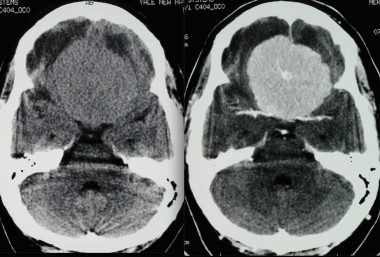

КТ при менингиоме

Компьютерная томография (КТ) часто используется для оценки опухолей мозга. Обычно на изображении без контрастного усиления она представлена в виде четко очерченного внемозгового (экстрааксиального) образования с ровными краями, прилегающего к твердой мозговой оболочке. Примерно 70-75% обладают повышенной плотностью по сравнению с окружающей их паренхимой головного мозга, а около 25% — изоденсивны. Редкая группа опухолей (липобластный подтип) содержат включения жира и, таким образом, характеризуются пониженной рентгеновской плотностью.

Кальцинаты являются другой частой находкой; их обнаруживают в 20-25% случаев. Кальцинаты на КТ могут быть узловыми, точечными или сплошными плотными. Часто наблюдается вазогенный паренхиматозный отек окружающей мозговойо ткани, визуализирующийся на снимке как участок паренхимы пониженной плотности. В некоторых случаях отек настолько выражен, что, ввиду преимущественного поражения белого вещества, может выглядеть в виде пальцевидных зон низкой плотности. Впрочем, отек отсутствует примерно в 50% случаев вследствие медленного роста опухоли.

Внутривенное введение контраста помогает в оценке менингиомы: в более 90% случаев наблюдается интенсивное равномерное повышение плотности после введения контраста.

Неоднородный характер контрастирования может быть следствием некроза или, реже, кровоизлияния.

З адняя тенториальная менингиома на корональном КТ-изображении с контрастным усилением. К намету мозжечка прилежит объемное образование повышенной плотности с четкими краями. Визуализируются застой спинно-мозговой жидкости, легкий отек прилежащих тканей, гомогенный характер контрастирования, а также расширение желудочков.

Примерно 90% менингиом видны на КТ-изображениях. Основная роль КТ, по сравнению с МРТ, заключается в отображении изменений в подлежащих костях и наличия кальцинатов в опухоли.

Нетипичная КТ-картина является основной причиной ошибок в предоперационной постановке диагноза. Так, могут быть пропущены менингиомы задней черепной ямки . Кроме этого, КТ не в состоянии отобразить наличие кист во внутричерепных менингиомах. Ложно-отрицательные результаты могут быть получены при наличии кистозных образований в менингиомах головного мозга. К ложно-положительным результатам могут приводить обширные зоны отложения кальция в твердой мозговой оболочке, которые могут имитировать заболевание. Снизить число ошибок, обусловленных человеческим фактором, помогает второе мнение.

Анапластическая менингиома лобной доли. Н а КТ-изображении в режиме мозгового окна и костного окна Хаунсфильда видна крупная внутрикостная менингиома. Обнаруживаемые КТ-феномены неспецифичны и могут включать различные изменения от остеолиза до остеосклероза. Внутрикостные менингиомы составляют менее 1% опухолей костной ткани.